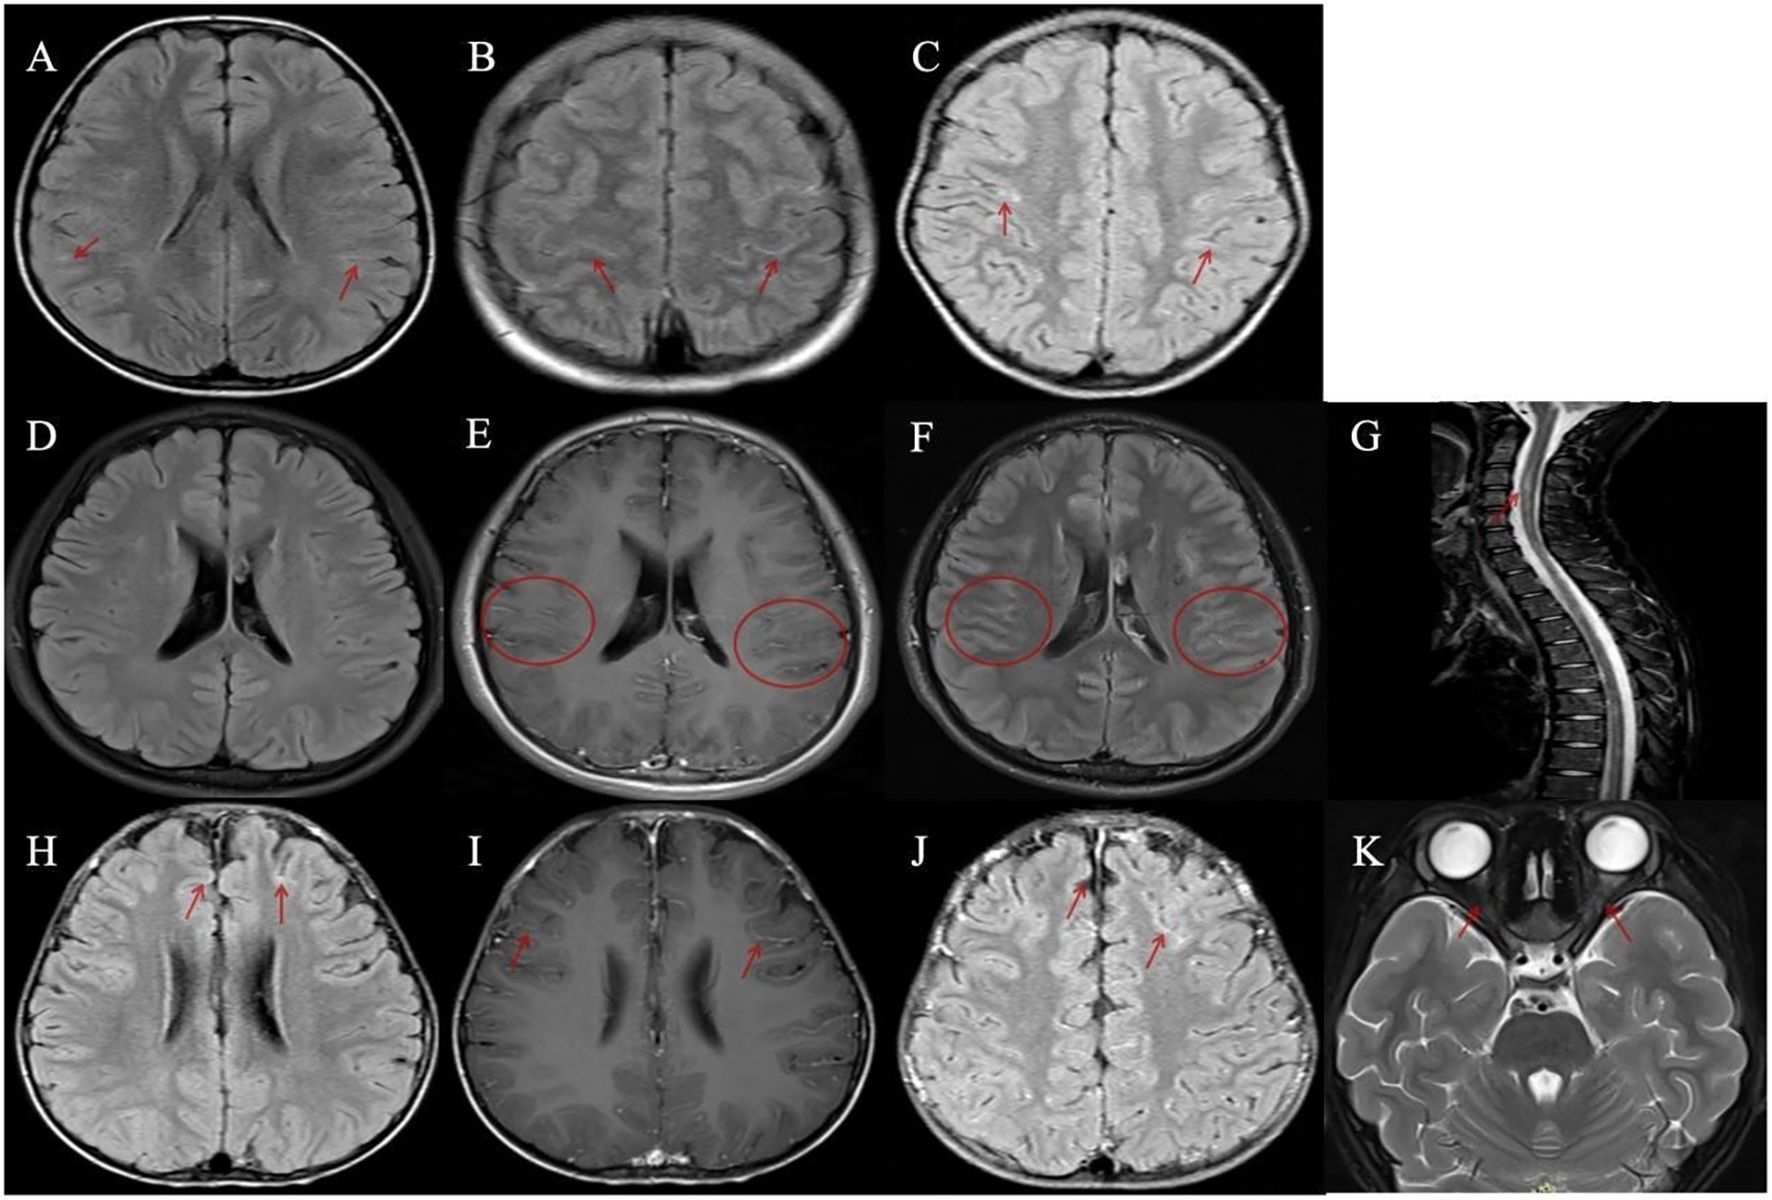

Brain MRI was performed in all 11 patients, with detailed findings summarized in Table 1. Among these patients, 4 (4/11, 36.4%) exhibited linear hyperintense signals along segments of the bilateral cerebral sulci on fluid-attenuated inversion recovery (FLAIR) sequences (Figures 1A–C, H), while 7 (7/11, 63.6%) showed no abnormal signals (Figure 1D). Gadolinium-enhanced brain MRI was performed in only 3 patients, with 2 showing leptomeningeal enhancement (LME) (Figures 1E, F, I, J) and 1 showing no contrast enhancement. Importantly, none of the 11 patients had radiological evidence of involvement in the cerebral cortex, subcortical white matter, or deep gray matter. Furthermore, orbital and spinal cord MRI were performed in all 11 patients, with no lesions detected.

Figure 1. Magnetic resonance imaging (MRI) findings in patients with meningeal abnormalities and contrast enhancement. (A–C, H) Four patients demonstrated linear hyperintense signals along the cerebral sulci on fluid-attenuated inversion recovery (FLAIR) sequences. (D–K) Two patients with disease relapse exhibited leptomeningeal enhancement. (D–G) A patient with recurrent myelitis: (D) FLAIR imaging showed no abnormal lesions; (E, F) Bilateral multiple leptomeningeal enhancements were observed on gadolinium-enhanced T1-weighted axial and FLAIR images; (G) Spinal MRI revealed multiple abnormal signals involving the cervical and thoracic spinal segments. (H–K) A patient with recurrent optic neuritis: (H) A representative image showed mild linear hyperintense signals along the cerebral sulci on FLAIR sequence; (I, J) Bilateral leptomeningeal enhancements were observed on gadolinium-enhanced T1-weighted axial and FLAIR images; (K) Orbital MRI demonstrated bilateral optic nerve swelling with abnormal signals.

One patient developed acute myelitis, manifesting as bilateral lower limb weakness and urinary retention. Spinal MRI revealed multiple abnormal signals in the cervical and thoracic segments of the spinal cord (Figure 1G), whereas electromyography (EMG) and cranial MRI showed no abnormalities. Notably, the serum MOG-IgG remained persistently positive at 8 months post-discharge. Another patient presented with bilateral optic neuritis, with clinical manifestations of bilateral blurred vision. Visual evoked potential (VEP) showed prolonged latency and reduced amplitude of the P100 wave. Orbital MRI indicated bilateral optic nerve thickening with abnormal signals (Figure 1K), while brain MRI was normal. This case also had persistently positive serum MOG-IgG, which was confirmed at 16 months post-discharge.